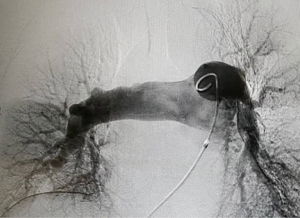

After 6 days of the support of ECMO and anticoagulation, the ECMO could not be weaned off, and TTE showed the persistent right atrial mass and severe pulmonary hypertension (Figure 1). In consideration of the ineffectiveness of ECMO support combined with anticoagulation, a discussion was held by the PERT; open-heart surgery was recommended, but the patient and his family members continued to refuse the open-heart surgery. On account of a previous report of successfully using of percutaneous thrombectomy to treat the right atrial mass, the patient and his family expressed willingness to receive the treatment of percutaneous thrombectomy (7). The patient was then referred to the digital subtraction angiography (DSA) room. During the angiography, no right atrial filling defect was found, and the intraoperative transthoracic echocardiogram confirmed the disappearance of the right atrial mass. Further pulmonary arteriography revealed embolisms in the main pulmonary arteries on both sides. There was a large round filling defect near the main pulmonary artery on the left main branch, and the exfoliated right atrial thrombus was considered (Figure 3). As the patient had a history of hypotension and elevated cardiac troponin I, a massive PE was diagnosed.

The AngioJet device was used to spray thrombolytics directly into the pulmonary arteries and entrain thrombi into the body of the catheter. However, sinus bradycardia and hypotension occurred when treating the main branches of the right pulmonary artery; so the AngioJet was withdrawn. After the heart rhythm and blood pressure were recovered, a 5-F pigtail catheter was rotated back and forth through the thrombus of the main branches of the right pulmonary artery except the right upper pulmonary artery branch (7).